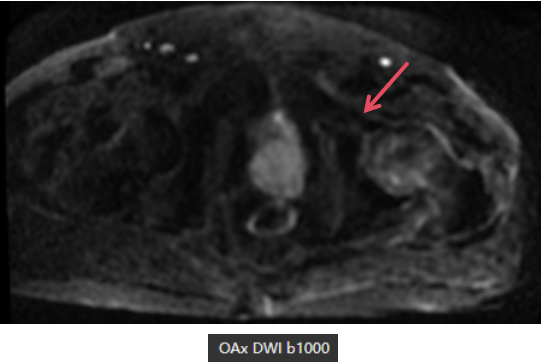

MR表现

左侧股骨头变扁,局部塌陷,骨质内见线状T1WI低信号,髋臼及股骨近端骨松质见片状T1WI低、T2WI压脂高信号,DWI高信号,周围滑膜增厚,邻近软组织肿胀,PD压脂信号增高,关节腔少量积液。